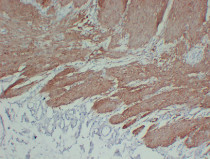

ARG66482 anti-Calponin 1 antibody IHC-P image

Immunohistochemistry: Paraffin-embedded Human laryngeal squamous cell carcinoma stained with ARG66482 anti-Calponin 1 antibody at 1:200 (4°C, overnight). Antigen Retrieval: Citric acid buffer (pH 6.0) was used.